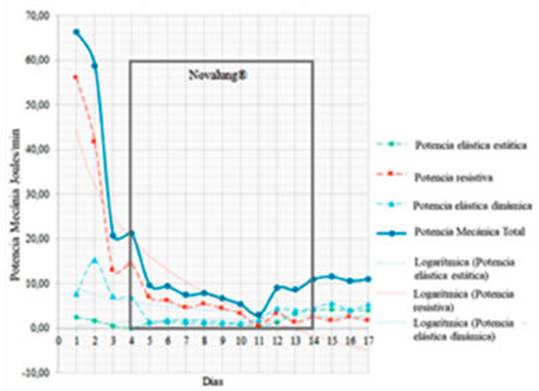

Al analizar la PM en sus componentes específiÂcos: potencia

elástica estática (asociada a la PEEP), potencia elástica

dinámica (asociada al VT)

y “poÂtencia resistiva” (vía aérea nativa), observamos que la

caída de la PM se debió principalmente a la reducción del

componente resistivo, que en el estaÂtus asmático sería

teóricamente el más importante. En nuestro caso, este componente

alcanzó más del 80% de la PM total en el primer día

(Figura 2).

la FR disminuye la ventilación minuto (VE), princiÂpal responsable de la hiperinsuflación dinámica.9 Veinticuatro horas

después de la instalación del Novalung®

se observó el impacto de la reducción de FR y del VT en la “potencia resistiva”, la

cual disminuyó de 58 J/min a 14,6 J/min.

La PM considera todos los elementos incluidos en la

ecuación de Otis; la DP y la FR son los comÂponentes más

agresivos sobre el fibroesqueleto pulmonar.10

Por otra parte, el flujo pico también es una variable

importante en el desarrollo del daño epitelial alveolar (Figura 3), en

consecuencia, la reducción del flujo inspiratorio evita la

disrupción del epitelio respiratorio. Este fenómeno ha sido

demostrado en un modelo in vitro por TschumÂperlin.11 En nuestro paciente, la

disminución de la FR permitió prolongar el tiempo espiratorio,

con lo que se pudo prolongar simultáneamente el tiempo inspiratorio y

reducir así el flujo pico.

El impacto de la PM se ha estudiado en el sínÂdrome de

dificultad respiratoria aguda (SDRA), pero no lo suficiente en la

descompensación asmáÂtica.12-14 No obstante, independientemente

de los parámetros específicos de daño, ya sea potencia

elástica dinámica (SDRA) o potencia resistiva (esÂtado

asmático), la energía mecánica se transfiere

inevitablemente al fibroesqueleto pulmonar en cada

ciclo mecánico.

El componente resistivo de la PM debe ser analizado siempre en

pacientes con obstrucción de la vía aérea. Al analizar los

componentes por separado, el componente resistivo (línea roja) se

destaca claramente como el principal generador de PM en este tipo de pacientes

(Figura 2).